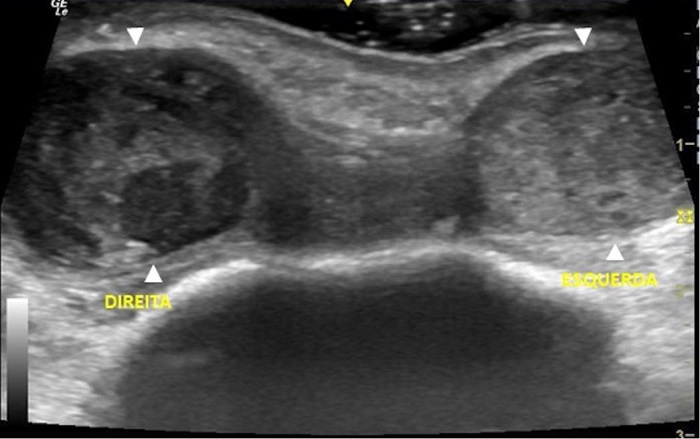

Diante do ocorrido, foi suspenso novamente o anticoagulante. O paciente foi reavaliado após 14 dias do procedimento e as nodulações haviam aumentado de tamanho (Figura 3). Nesse momento, o paciente foi encaminhado para avaliação ultrassonográfica com o objetivo de elucidação diagnóstica. Foi realizado exame ultrassonográfico com Doppler colorido (Logiq E, GE Medical System CO. LTD.), utilizando-se transdutor multifrequencial linear de 12MHz, que demonstrou dois nódulos hipoecoicos na região frontal bilateral, sem fluxos compatíveis com hematomas (Figura 4).

O hematoma à direita apresentava ecotextura heterogênea e media 2,9 x 1,4 x 2,2cm. No interior deste nódulo, destacava-se outro nódulo anecoico, de limites bem definidos, medindo 0,7 x 0,7cm, que apresentava fluxo bidirecional ao exame com Doppler colorido, fluxo alimentado pela artéria supratroclear direita que, por sua vez, localizava-se superficialmente na periferia do hematoma (distando 0,3cm da epiderme) (Figura 5). À esquerda, o hematoma apresentava ecotextura mais homogênea em relação ao lado contralateral, media 2,2 x 1,3 x 1,8cm, e a artéria supratroclear esquerda localizava-se profundamente (distando cerca de 1,0cm da epiderme) na periferia do hematoma.